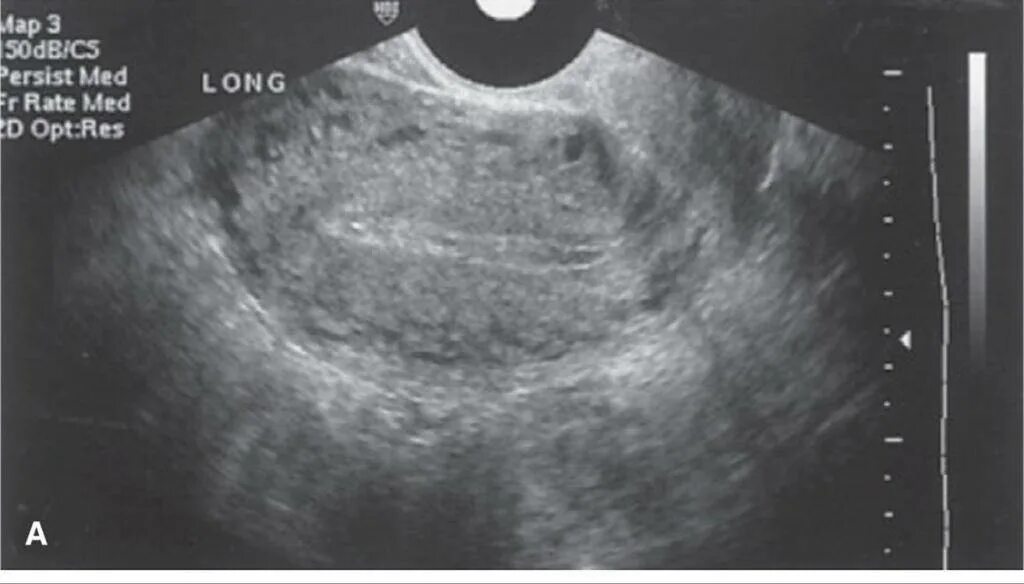

Узи при месячных